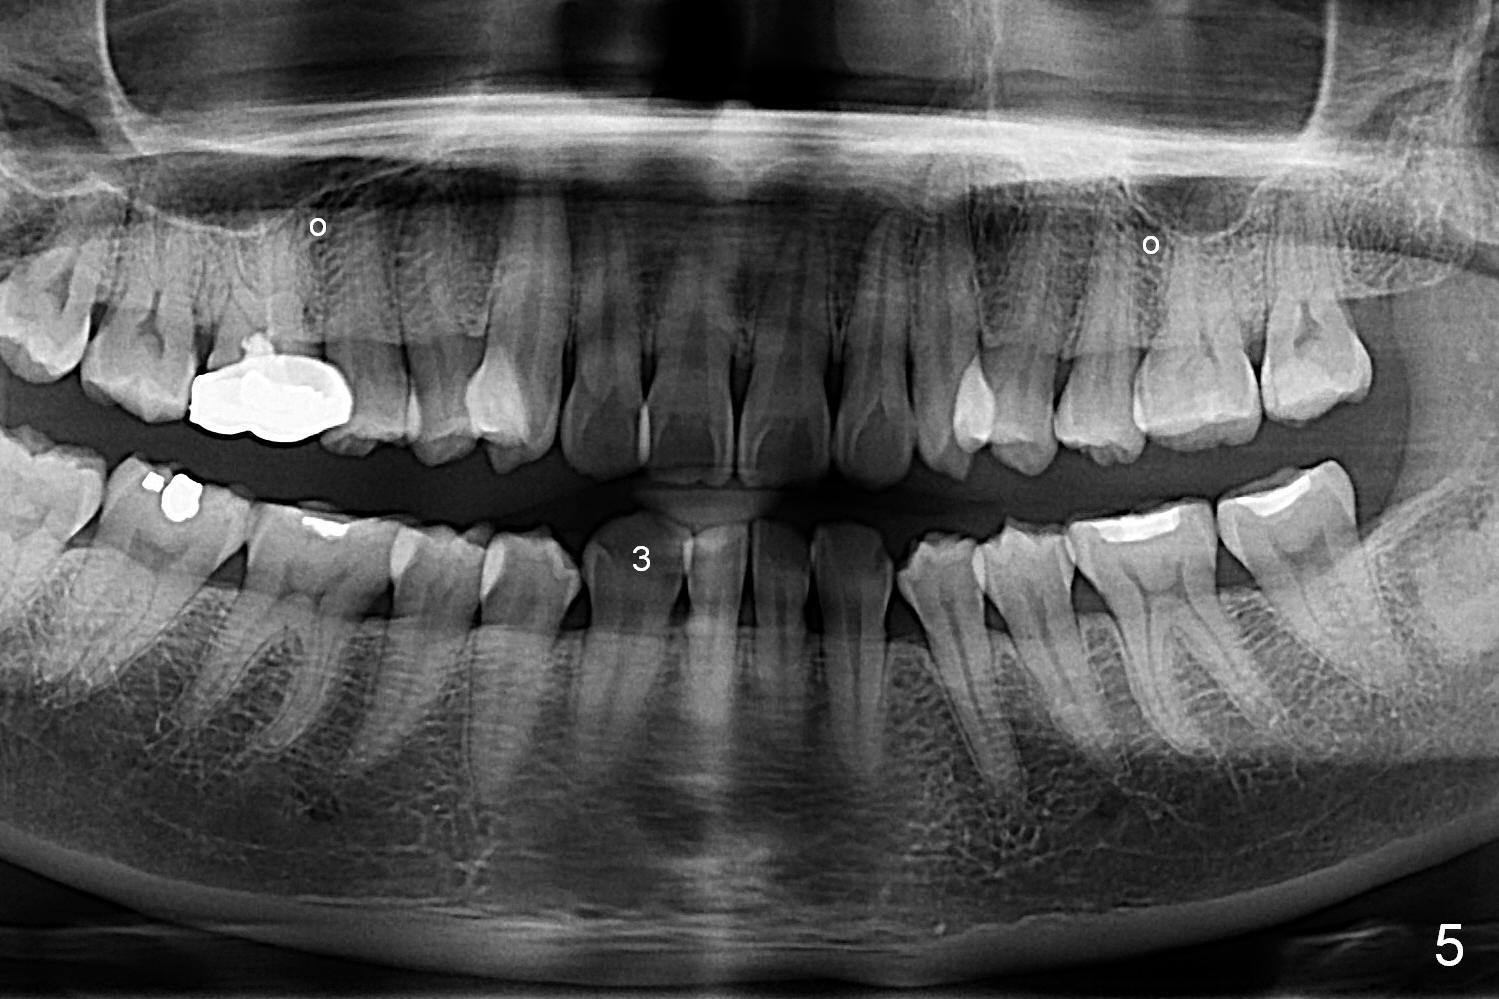

A 41-year-old woman requests orthodontic treatment because of the upper blocked out canines (Fig.6,8). Her facial and dental midlines coincide (Fig.1). Her profile is slightly convex (Fig.2,3) with increase in overjet (Fig.4). Orthodontic treatment includes extraction of U4s and placement of 2 mini-implants between U5 and 6 (Fig.5 o) when arch wires change to 18x25. Power arms (as high as possible) are placed between U2 and 3. U1-3s are retracted at the same time (en mass) because of absolute anchorage of the mini-implants. Retraction time will be reduced. Interproximal reduction (IPR) will be done especially at LR3 (macrodontia, Fig.5) if the lower arch turns out to be too large.

The rotation of the upper canines is not corrected much in the next 3.5 months (Fig.21, as compared to Fig.18). Distalization of the upper right canine is implemented by power chain, but this is not sufficient because of the anterior deep bite. Note the tension of 18 niti wire between LR 3 and 4 (^). Mini implants are going to be placed mesial or distal to L3s (Fig.22,23 circles) to intrude the lower anterior teeth with elastic or power chain (Fig.23 red line, 24 black area). The upper anteriors will have space to be distalized (Fig.24 arrow). If necessary, proximal reduction will be accomplished at LR3 (extra wide, Fig.25 black outline) for further overjet correction (arrows).